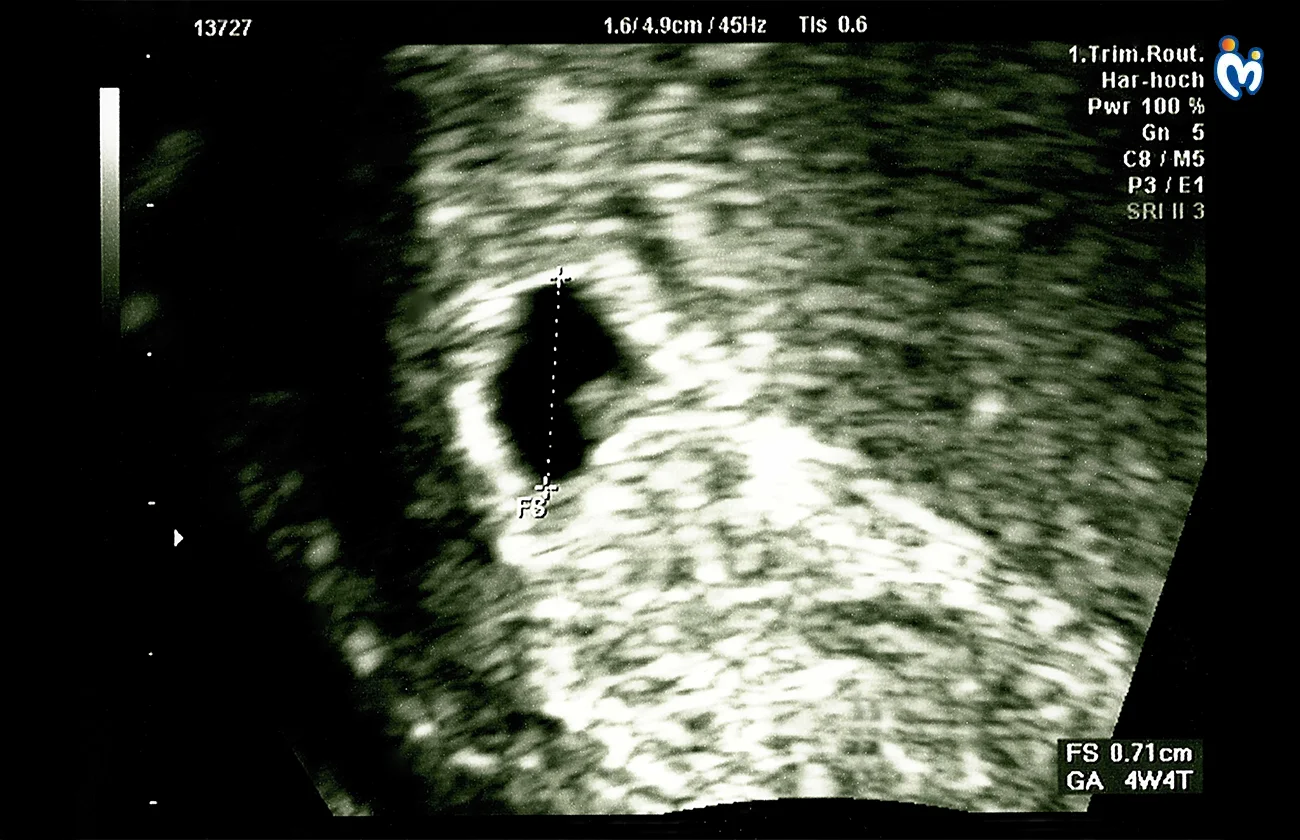

Your baby now has two layers of cells, which will later develop into organs.